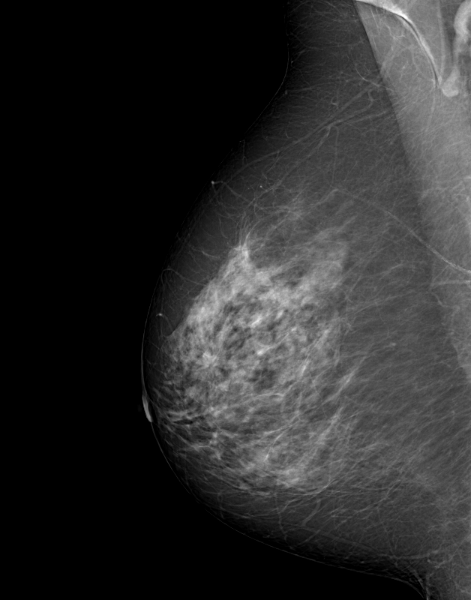

A 69 year-old woman, with no personal or family history of breast or ovarian cancer, referred for routine screening mammography.

The breasts are dense type C according to the BI-RADS classification.

There was some hesitation around an area of architectural distortion that was very difficult to visualize on 2D imaging without the help of AI on a single incidence: this image could have gone unnoticed in the patient flow.

MammoScreen however immediately spotted this anomaly on the 2 incidences with a high suspicion score of 9.

A tomosynthesis and ultrasound scan are performed at the patient’s arrival, confirming the presence of an attenuating mass and irregular contours classified as BI-RADS 5 at the union of the external quadrants of the right breast, at 9h 3 cm and measuring 8x7x8 mm.